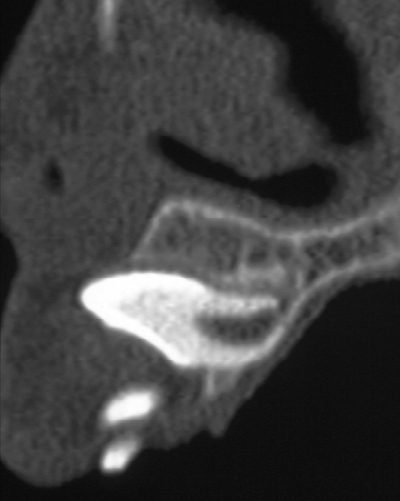

9歳の男児。上顎左側中切歯が生えてこないことを主訴として来院した。初診時の口腔内写真、エックス線画像及び歯科用コーンビーム CT 矢状断像を別に示す。

今後、⎿1において起こり得る異常はどれか。1つ選べ。